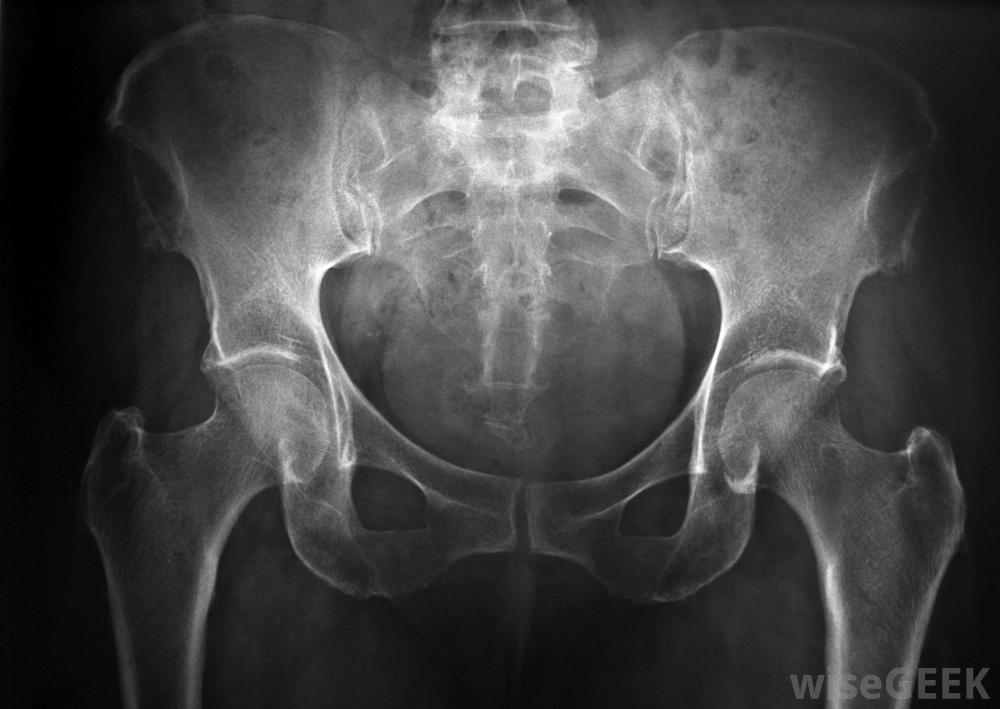

X光片可用于诊断骶髂关节炎症当出现背痛的第一个征兆时,与医生交谈是很重要的,这样才能做出准确的诊断。医生可以通过进行体格检查、询问症状和对关节进行x光检查来诊断骶髂关节的问题。医生调查其根本原因很重要,非甾体抗炎药(NSAIDs)可能有助于对抗骶髂关节炎症和疼痛在轻度病例中,如果确定原因是急性损伤或过度使用关节,医生通常建议病人在家里治疗骶髂关节炎。病人通常被要求休息几天或几周,避免剧烈的体力活动。冰袋可以帮助止痛消肿,外用软膏可以缓解皮肤组织的刺激。许多病人服用非处方消炎药来进一步减轻症状。当一个人遵照医生的指示治疗骶髂发炎时,症状往往会在两到四周内消失